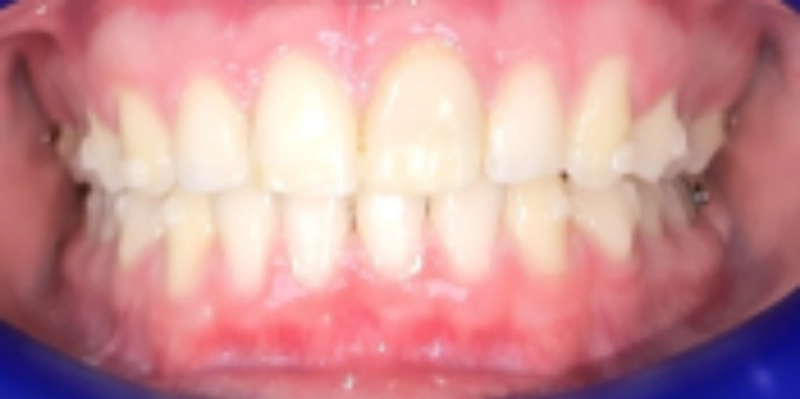

תמונות לפני ואחרי טיפול

לפני

ק.ר., בן 12, הגיע למרפאה עם מקרה אורתודונטי מורכב, שכלל שילוב של בעיה סגרית, צפיפות דנטלית ואתגר אסתטי משמעותי באזור הקדמי. בבדיקה נמצא סגר עובר אופקי מוגדל, סגר אסימטרי עם יחסי קלס 2 בצד ימין באזור הטוחנות, יחס טוחנות תקין בצד שמאל, אך יחסי קלס 2 באזור הניבים בשני הצדדים. בנוסף נצפתה צפיפות באזור החותכות העליונות, עם חפיפה בין שיניים 11 ו 21, וכן צפיפות גם בקשת התחתונה.

בקשה מרכזית של המטופל והמשפחה הייתה לבצע את הטיפול באמצעות קשתיות שקופות. במקרה זה, הבחירה בקשתיות לא נבעה רק משיקול אסתטי. להפך, היתרון המרכזי של הקשתיות היה היכולת לתכנן תנועה מדויקת, סלקטיבית ומדורגת, באזורים מסוימים בלבד, בלי לחייב הפעלה של כל השיניים בקשת באותו שלב. כך ניתן היה להשאיר את שן 21 במקומה לאורך חלקים משמעותיים מהטיפול, בזמן ששאר המשנן עבר יישור, תיאום ותיקון סגרי. זהו יתרון חשוב במיוחד במקרים שבהם יש שן אחת שדורשת זהירות ביולוגית גבוהה ואי אפשר לשלב אותה מיד במערכת הכוחות הכללית.